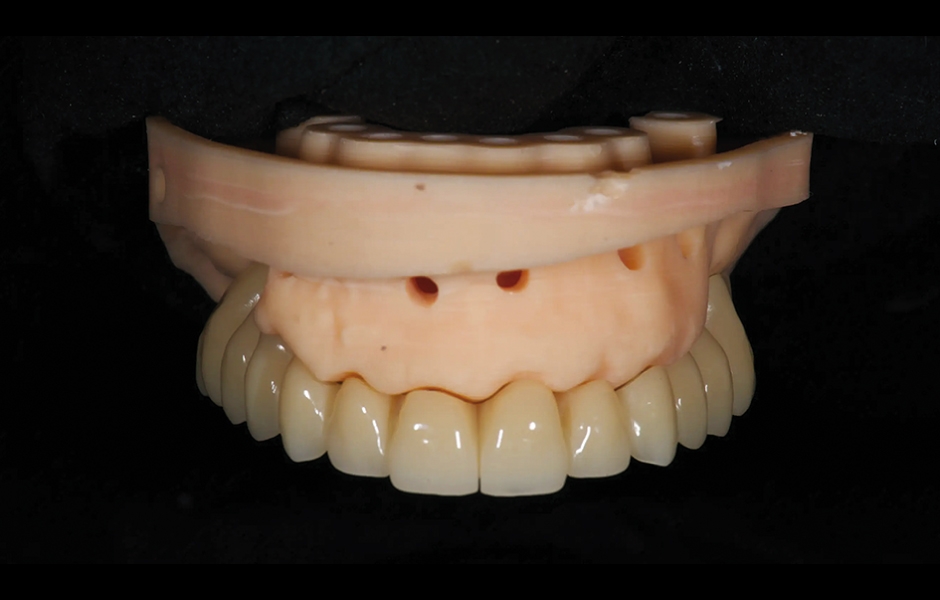

V den operace byla aplikována lokální anestezie a první chirurgická šablona byla stabilizována na zbývajících zubech k přípravě pěti fixačních pinů. Poškozené zuby byly extrahovány a druhá chirurgická šablona byla upevněna v připravených místech. Osm implantátů (Osstem TSIII SOI, Osstem Implant) bylo umístěno – pět do čerstvých extrakčních alveolů a tři do dříve zahojených oblastí. Všechny implantace proběhly plně navigovaně pomocí chirurgické šablony bez kovových pouzder a s dedikovanou chirurgickou sadou (OneGuide KIT, Osstem Implant; obr. 8). [11] Jeden implantát vyžadoval krestální sinus lift, který byl proveden plně navigovaným přístupem (OneCAS KIT, Osstem Implant; obr. 9). Xenogenní kostní materiál (A-Oss, Osstem Implant) byl použit k vyplnění extrakčních alveolů a dutiny sinu. [12] Na všechny implantáty byly okamžitě nasazeny multi-unit abutmenty a dočasné abutmenty (Osstem Implant) podle konceptu „one abutment, one time“. [13] Předem připravená dočasná protetika na bázi PMMA s kovovou výztuhou byla vložena a ihned fixována v ústech. V ordinaci byly provedeny úpravy pro dosažení správné okluze (obr. 10–12). Pacient obdržel pooperační instrukce a medikaci.

Obr. 10: Provizorní protetická práce s kovovou výztuhou.

Obr. 11: Provizorní protetická práce s kovovou výztuhou in situ, čelní pohled.